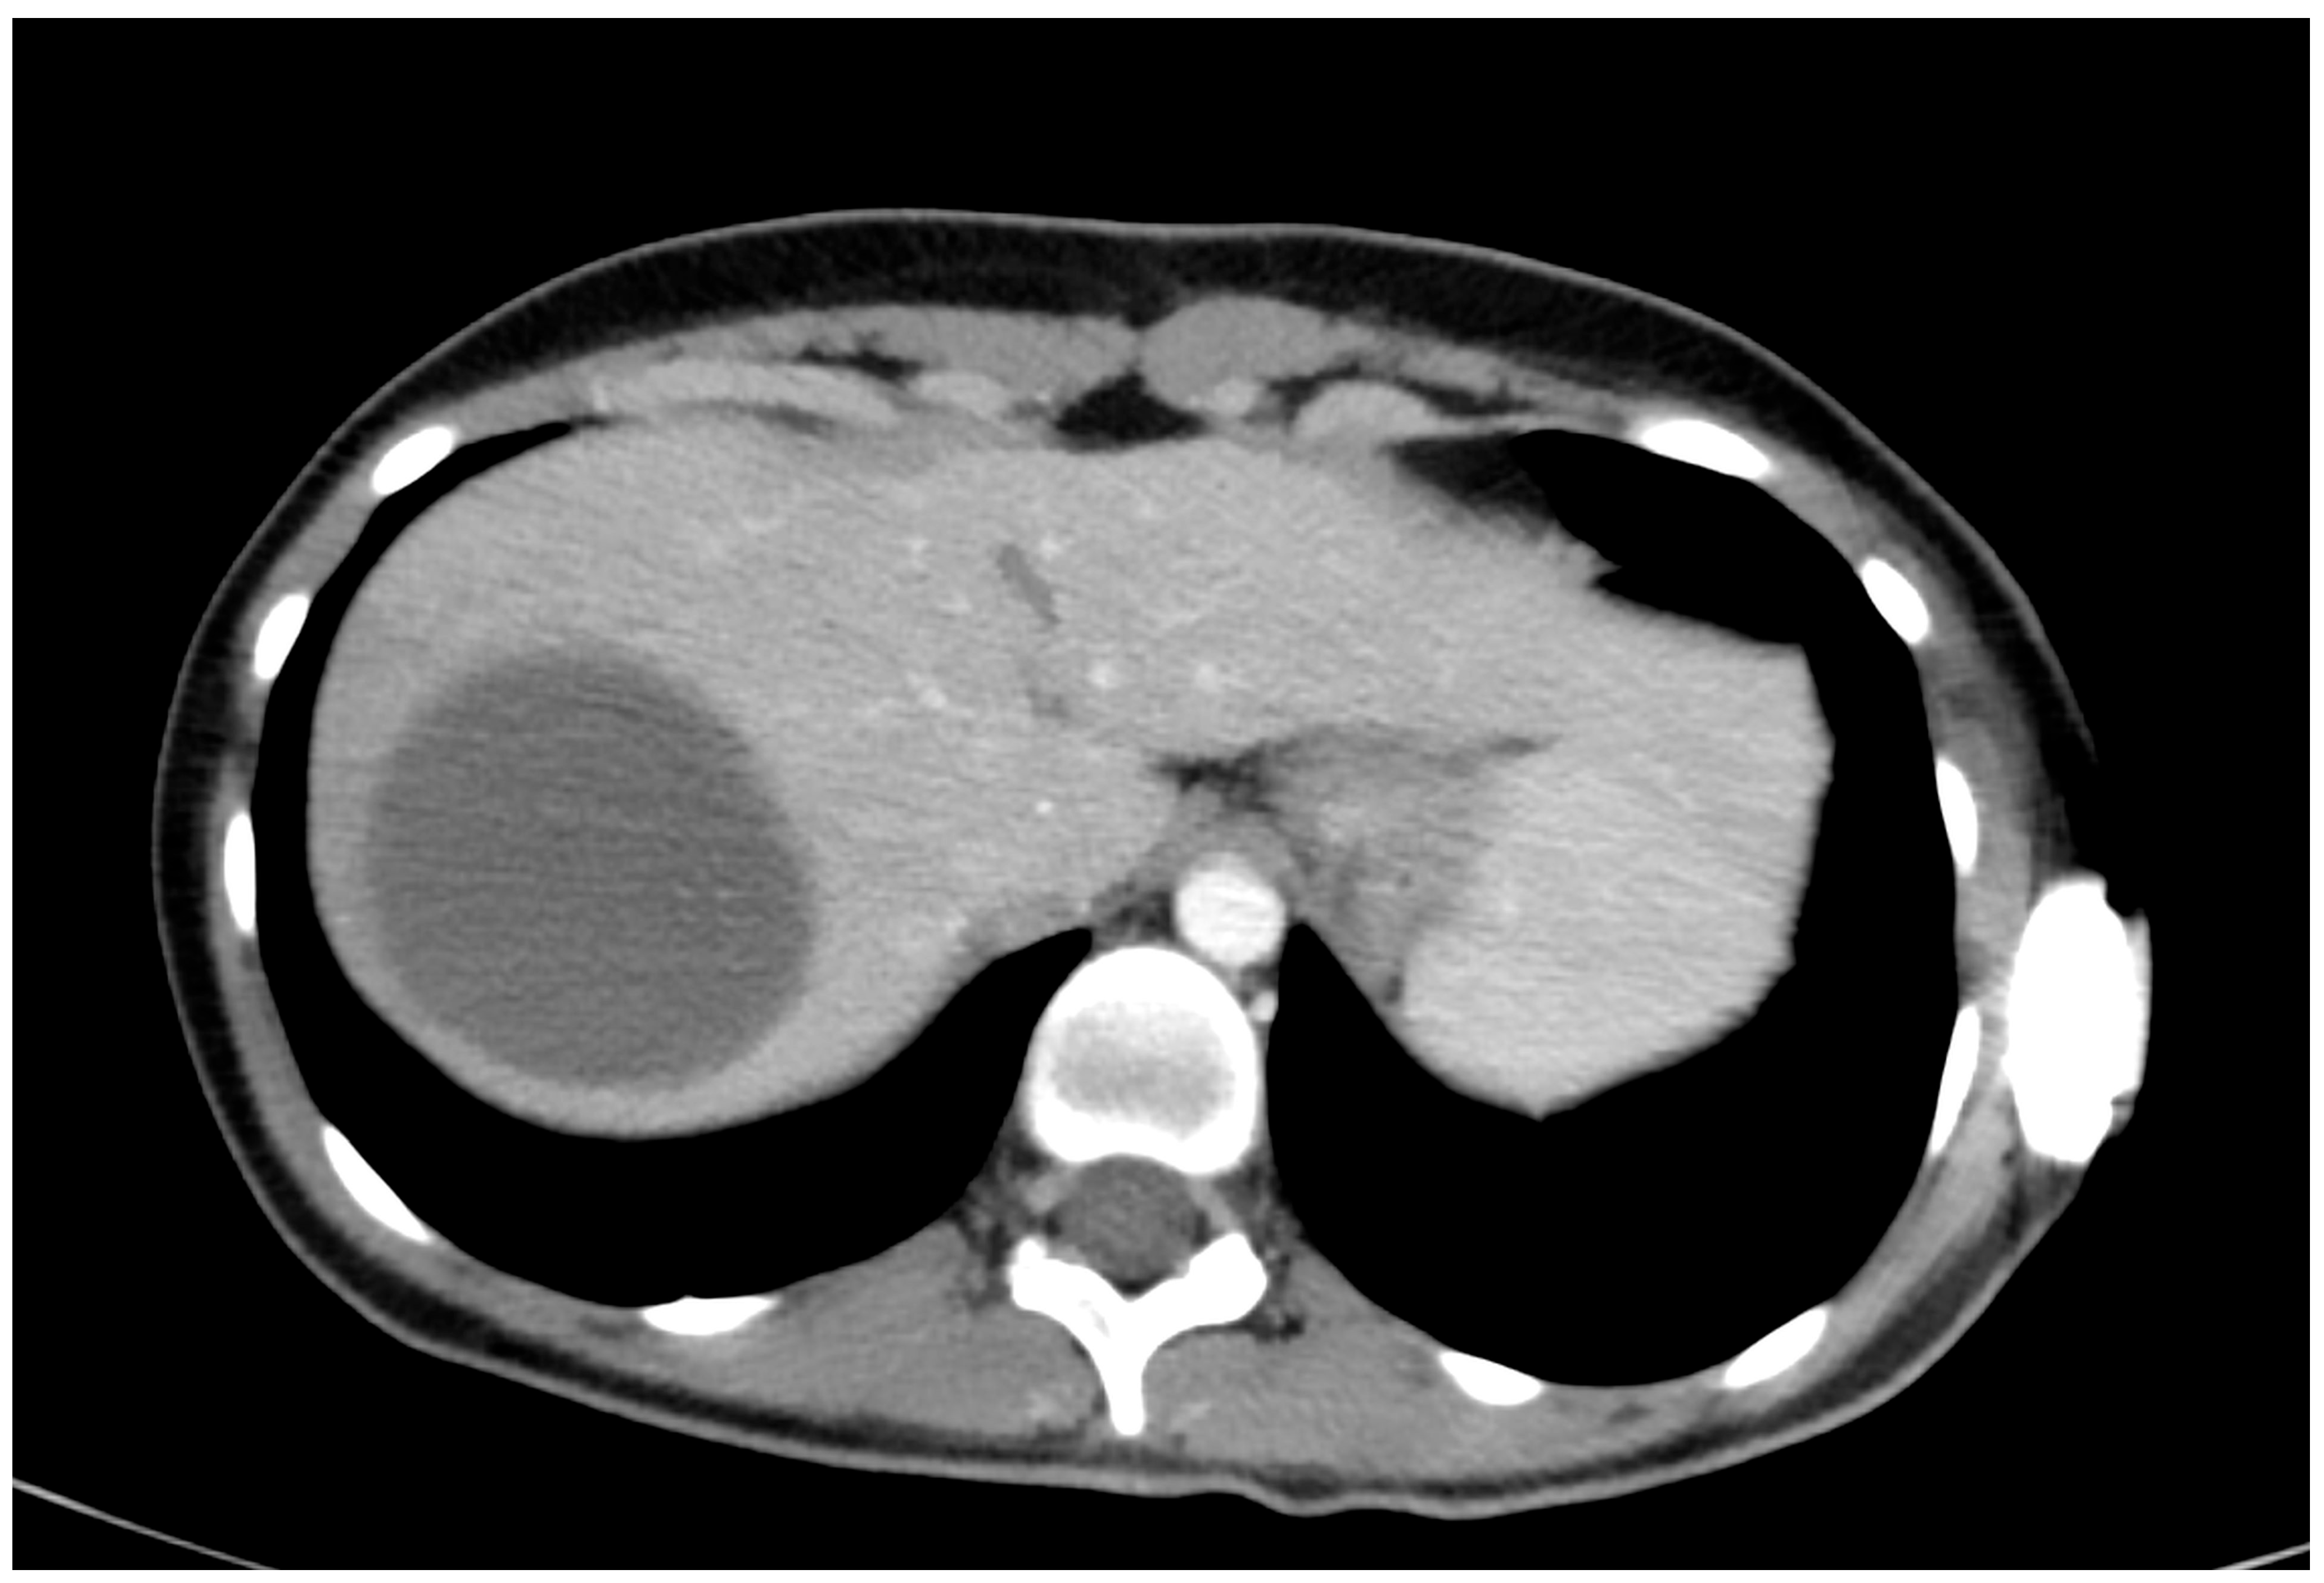

The only patient who received conservative treatment was stable after admission, and an MRI of the heart showed liver injury. Intraparenchymal haematoma of the liver without active bleeding was confirmed by CT scans (Figure 3). The haematoma was repeatedly re-evaluated by ultrasound (Figure 4), and the patient was later discharged.

Figure 3.

CT scan in patient with intraparenchymal haematoma and conservative treatment.